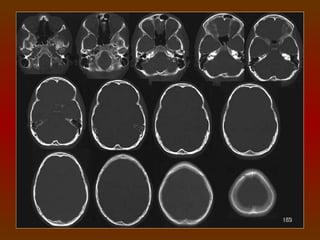

CORTE 5

a) Lobo frontal

b) Corno frontal do ventrículo lateral

c) Fissura silviana

d) Terceiro ventrículo

e) Glândula pineal (calcificada)

f) Plexo coróide (calcificado)

g) Lobo occipital

CORTE 6

c) Lobo parietal

d) Plexo coróide (calcificado)

e) Lobo occipital

f) Cápsula interna

g) Núcleo caudado

CORTE 7

b) Corpo do ventrículo lateral

d) Lobo occipital

e) Giros

f) Sulcos

CORTE 8

a) Fissura inter-hemisférica

b) Foice anterior do cérebro

c) Foice posterior do cérebro

d) Substância cinzenta

e) Substância branca

CORTE 9

a) Foice cerebral

b) Sulcos

c) Giros

CORTE 10

a) Sulcos

b) Foice cerebral

c) Circunvoluções

TC CRÂNIO AXIAL

COM JANELA ÓSSEA